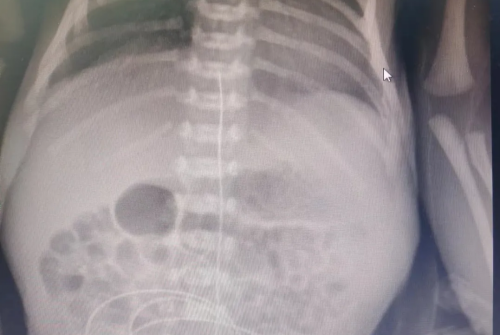

为尽快解决患儿体重增长缓慢的问题,医务人员拟为患儿实施“脐静脉导管置入术”为其治疗。当天,在市中心医院帮扶老师的指导下,顺利实施院内首例“脐静脉导管置入术”,置管后,经过规范化治疗和精细化护理,该患儿已于近日顺利康复出院。此项技术的成功开展标志着区人民医院儿科(新生儿科)危重新生儿救治水平再上新台阶。

技术介绍:脐静脉置管(UVC)是新生儿重症监护病房救治危重新生儿的重要技术。主要适用于早产儿(极低和超低出生体重儿)、窒息复苏、换血、需要中心静脉、紧急血管通路等。

置管后可以避免长期反复静脉穿刺,从而减轻新生儿的痛苦。脐静脉置管可以进行高渗液体,比如脂肪乳,以及钙剂等的输入,避免血管的刺激而引起静脉炎、血管钙化。脐静脉置管后可以保留两周左右,对于长期住院,尤其是早产儿、低出生体重儿、极低出生体重儿的治疗,是十分有必要的。(齐芸)